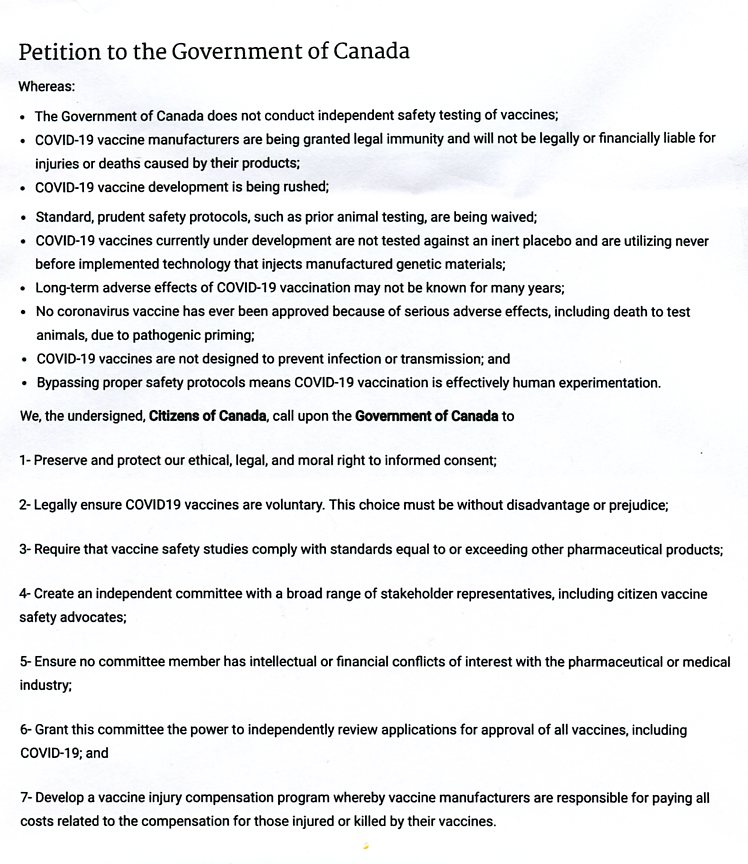

COVID VACCINE HUMAN EXPERIMENT PETITION

(for sake of health & life sign the petition)